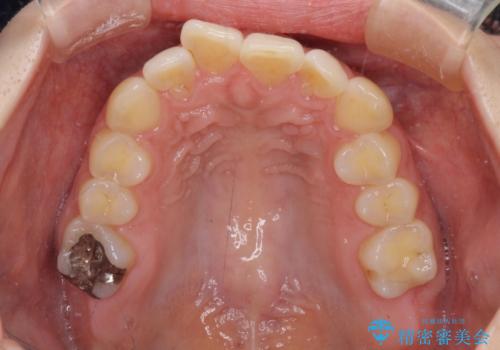

上顎前歯が捻れて前方に飛び出しており、下顎前歯もそれに沿うようにデコボコとなっていました。

IPR(歯と歯の間を削る処置)によりスペースを獲得して上下顎前歯のデコボコを改善し、飛び出している前歯が引っ込むように設定し、インビザラインにて矯正治療を行うこととしました。

左右ともに、上顎第二大臼歯が欠損しており、下顎の第二大臼歯が十分に咬み合う歯がない状態のため、放置しておくと下顎の奥歯が挺出してくる可能性があります。

安定した咬み合わせを維持するためにも、将来的に上左右にインプラント補綴が必要となります。